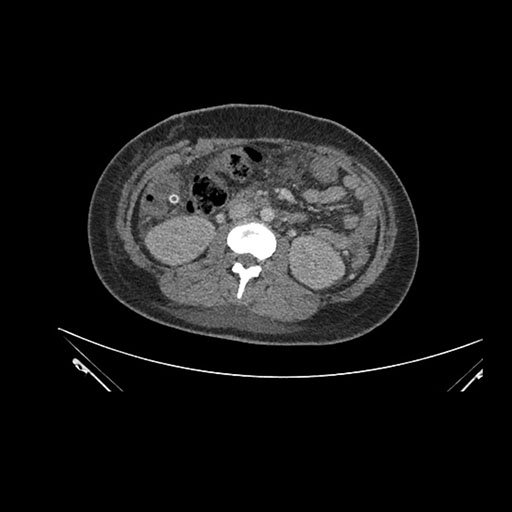

Imaging Analysis

Look through the patient's CT scan to identify any areas of concern for the necessary procedure.

Axial Venous

Coronal Venous

Based on initial findings, which issue(s) would you be most concerned about?